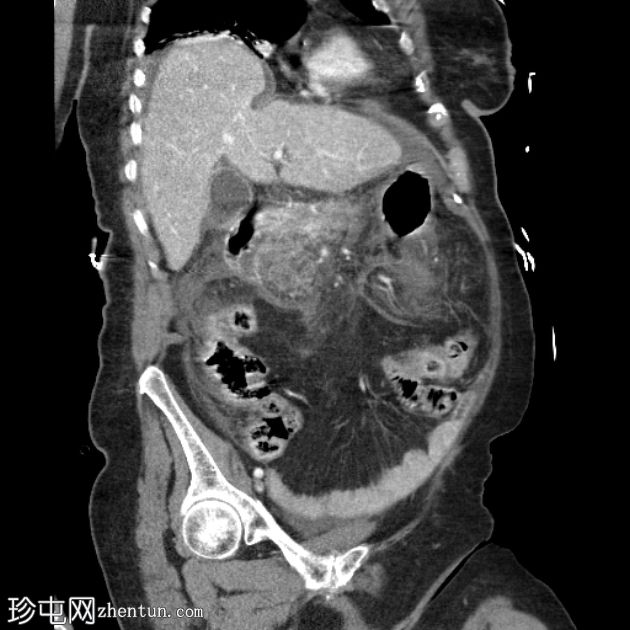

轴位增强扫描(门静脉期)

胰腺弥漫性肿大,实质呈不均匀强化,胰头、胰体远端和胰尾可见大片无强化坏死区域(坏死胰腺实质>50%)。胰周脂肪间隙模糊,胰周、肠系膜根部、左右肾前间隙可见多发性急性坏死灶(ANC)。

门静脉、脾静脉和肠系膜静脉通畅。未见血管并发症。

轻度腹腔和盆腔腹水,伴大网膜和腹膜增厚及模糊影。

胃、十二指肠、小肠和大肠壁增厚,可能为反应性改变。

该病例表现为急性坏死性胰腺炎,伴大面积无强化实质坏死(>50%胰腺实质),以及急性胰周坏死积液(ANC持续时间<4周)。Balthazar评分E级,胰腺坏死>50%,CT严重程度指数10。胰酶升高确诊。患者紧急入住ICU。